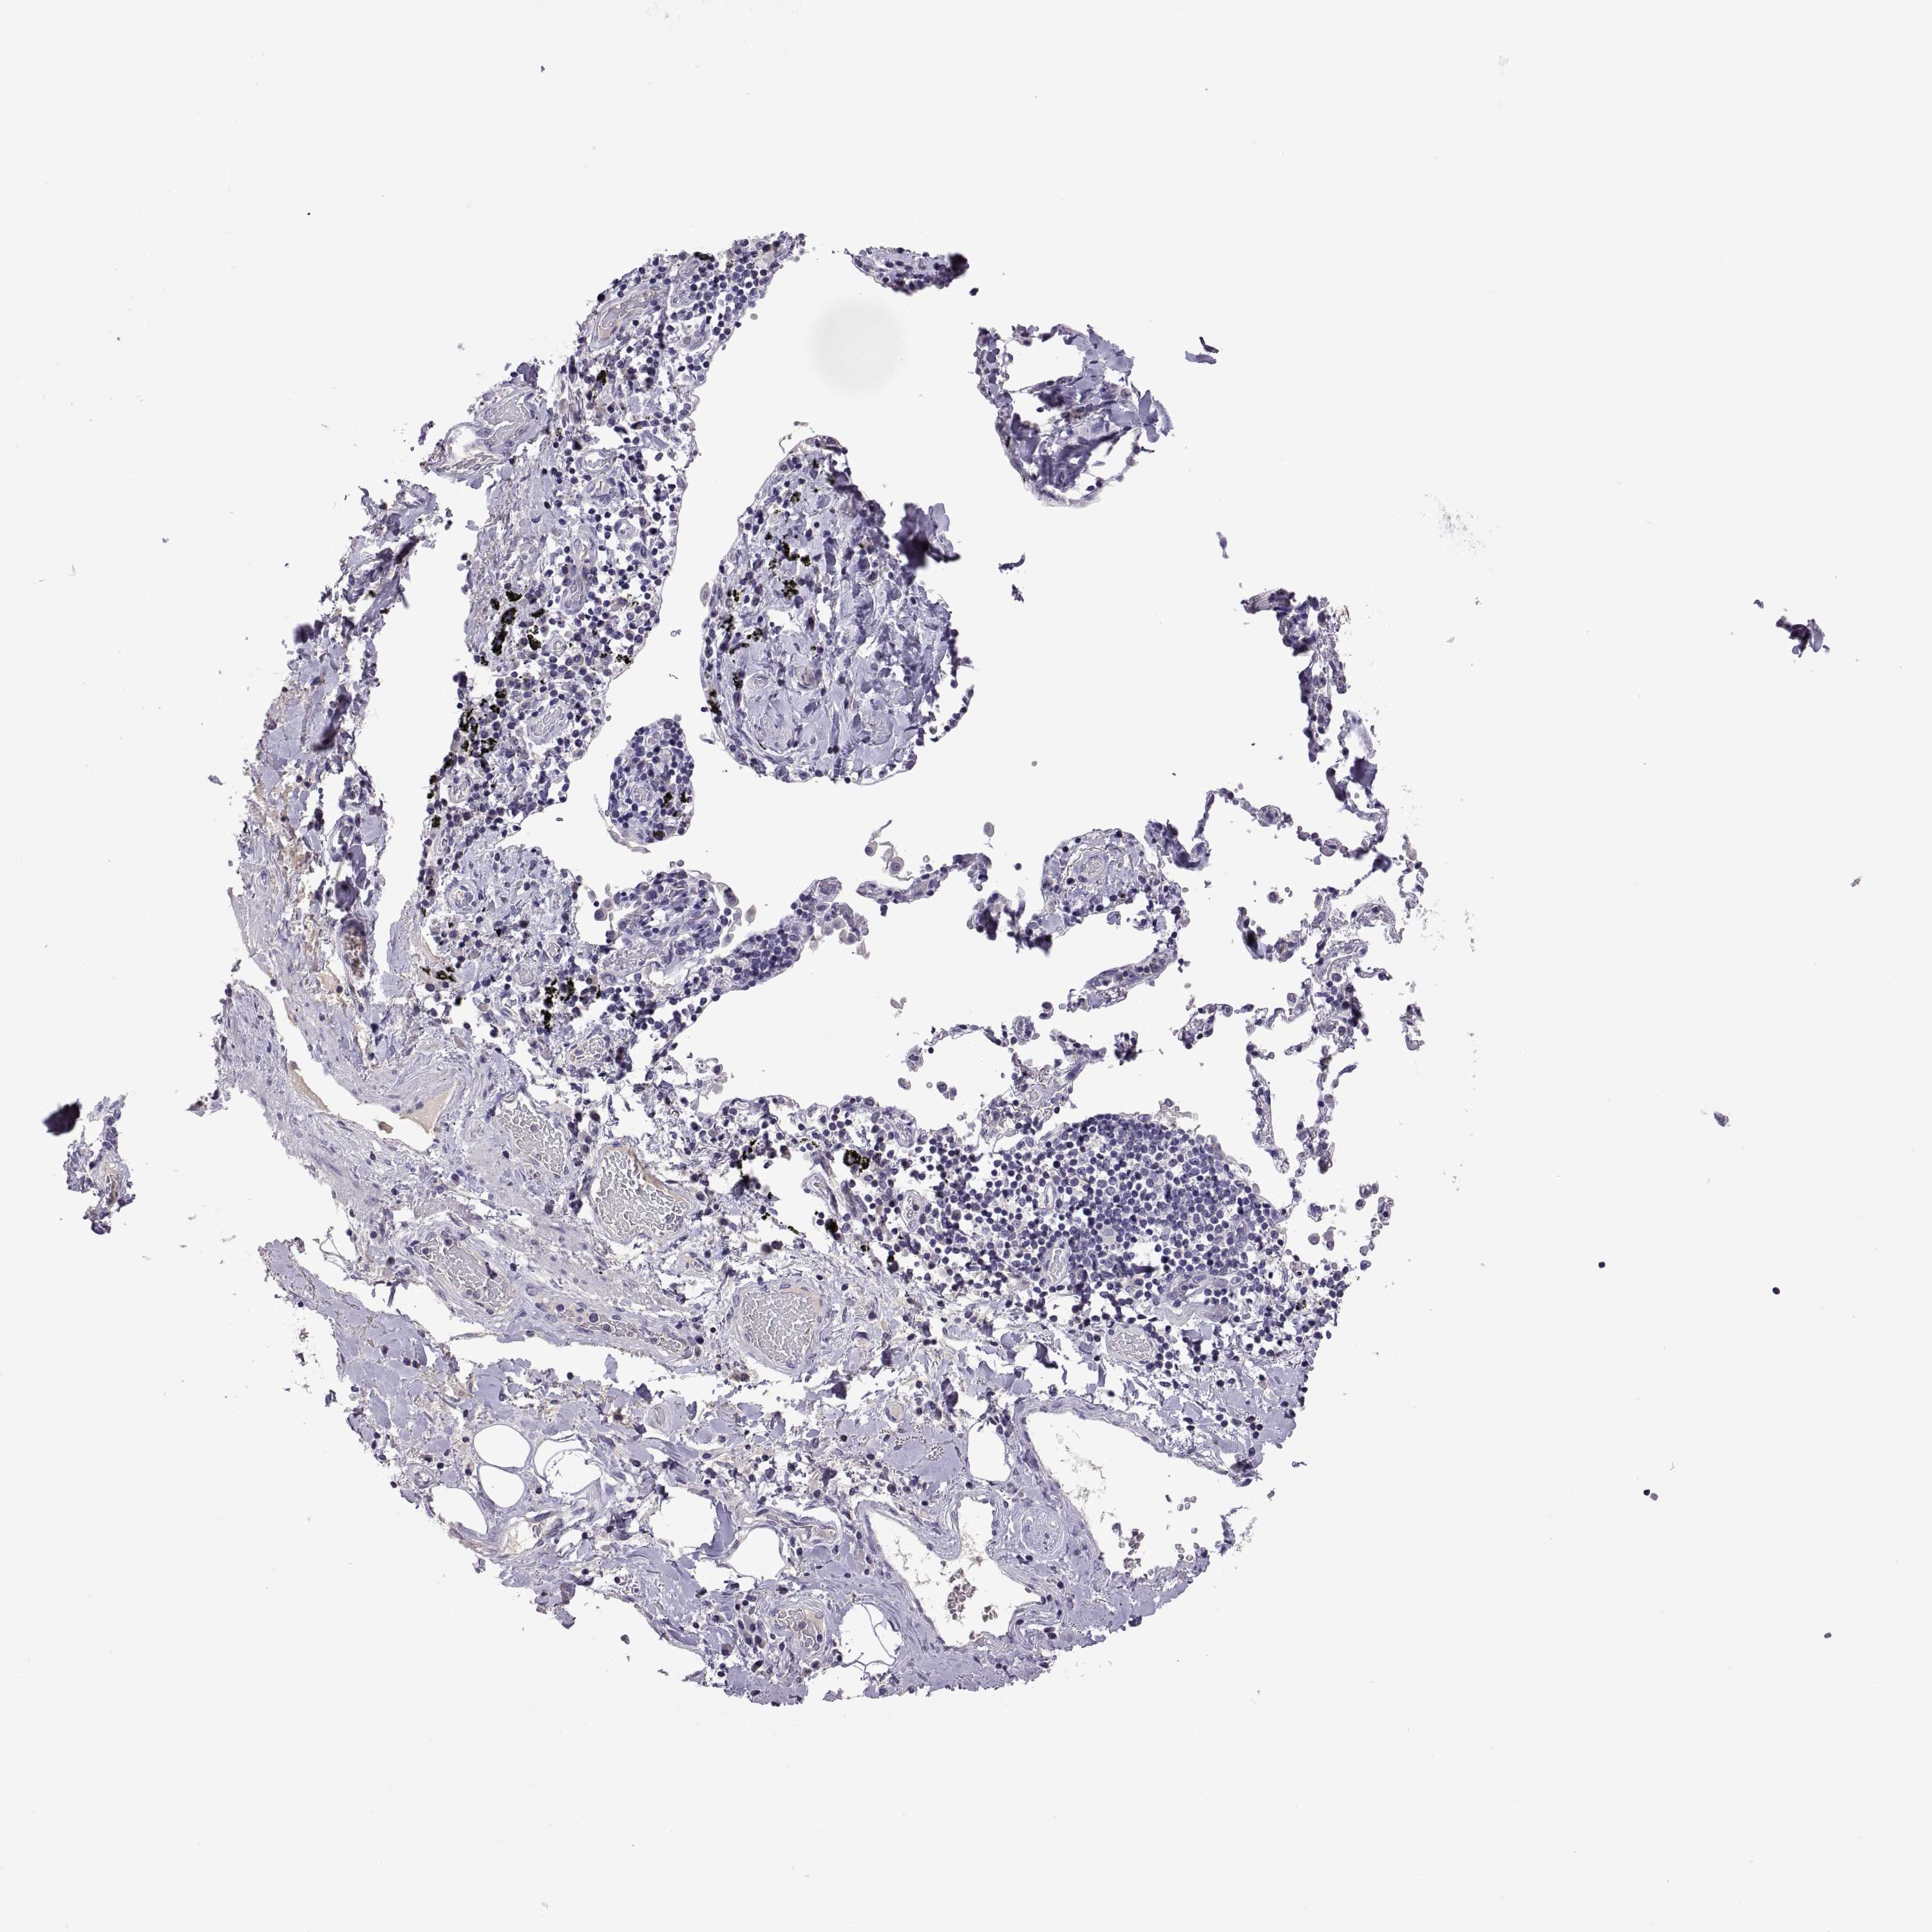

CANCER LUNG CANCER Show tissue menu

LUAD TCGA LUAD VALIDATION LUSC TCGA LUSC VALIDATION PROTEIN LUAD CPTAC PROTEIN LUSC CPTAC PROTEIN EXPRESSION

LUNG ADENOCARCINOMA (TCGA) - Interactive survival scatter ploti

The Survival Scatter plot shows the clinical status (i.e. dead or alive) for all individuals in the patient cohort, based on the same data that underlies the corresponding Kaplan-Meier plots. Patients that are alive at last time for follow-up are shown in blue and patients who have died during the study are shown in red.

The x-axis shows the expression levels (FPKM) of the investigated gene in the tumor tissue at the time of diagnosis. The y-axis shows the follow-up time after diagnosis (years). Both axes are complimented with kernel density curves demonstrating the data density over the axes. The top density plot shows the expression levels (FPKM) distribution among dead (red) and alive patients (blue). The right density plot shows the data density of the survived years of dead patients with high and low expression levels respectively, stratified using the cutoff indicated by the vertical dashed line through the Survival Scatter plot. This cutoff is automatically defined based on the FPKM cutoff that minimizes the p-score. The cutoff can be changed by dragging the vertical line or by entering a cutoff value in the square labeled "Current cut-off".

Under the Survival Scatter plot the p-score landscape (black curve; left axis) is shown together with dead median separation (red curve; right axis). Dead median separation is the difference in median mRNA expression between patients who have died with high and low expression, respectively. It is calculated as follows: median FPKM expression of dead patients with high expression - median FPKM expression of dead patients with low expression. This is intended to aid the user in visually exploring custom cutoffs and the associated p-scores and dead median separation.

Individual patient data is displayed and can be filtered by clicking on one or more of the category buttons on the top of the page. Categories describing expression level and patient information include: high, low, alive, dead, female, male and tumor stages. The scale of the x-axis can be toggled between linear and log-scale by clicking on the "x log" button. Mouse-over function shows TCGA ID, patient information and mRNA expression (FPKM) for each patient.

& Survival analysisi

Kaplan-Meier plots summarize results from analysis of correlation between mRNA expression level and patient survival. Patients were divided based on level of expression into one of the two groups "low" (under cut off) or "high" (over cut off). X-axis shows time for survival (years) and y-axis shows the probability of survival, where 1.0 corresponds to 100 percent.

TBX19 is not prognostic in Lung Adenocarcinoma (TCGA)

TCGA RNA samplesi

RNA-seq data is reported as average FPKM (number Fragments Per Kilobase of exon per Million reads), generated by the The Cancer Genome Atlas (TCGA) .

Normal distribution across the dataset is visualized with box plots, shown as median and 25th and 75th percentiles. Points are displayed as outliers if they are above or below 1.5 times the interquartile range. FPKM values of the individual samples are presented next to the box plot.

Average pTPM 1.7

Number of samples 497